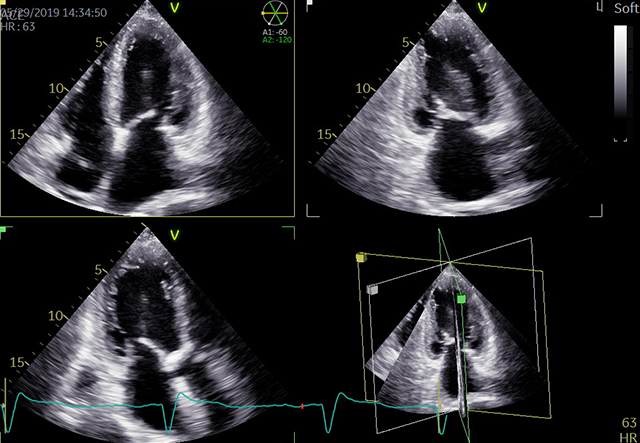

心エコー検査

心エコー検査は、超音波検査とも呼ばれ、胸に小さな機器(プローブ)を当てるだけでリアルタイムに心臓の動きの度合い、大きさ、さらには弁逆流などを診断することができます。最近は3D技術も導入され、より詳細な情報を得ることができるようになりました。

循環器診療には欠かせない、重要な検査です。当院で用いている装置はGEヘルスケア社製 VividE95が2台とPhilips社製 Affiniti 70G が2台。所要時間は20〜30分程度です。